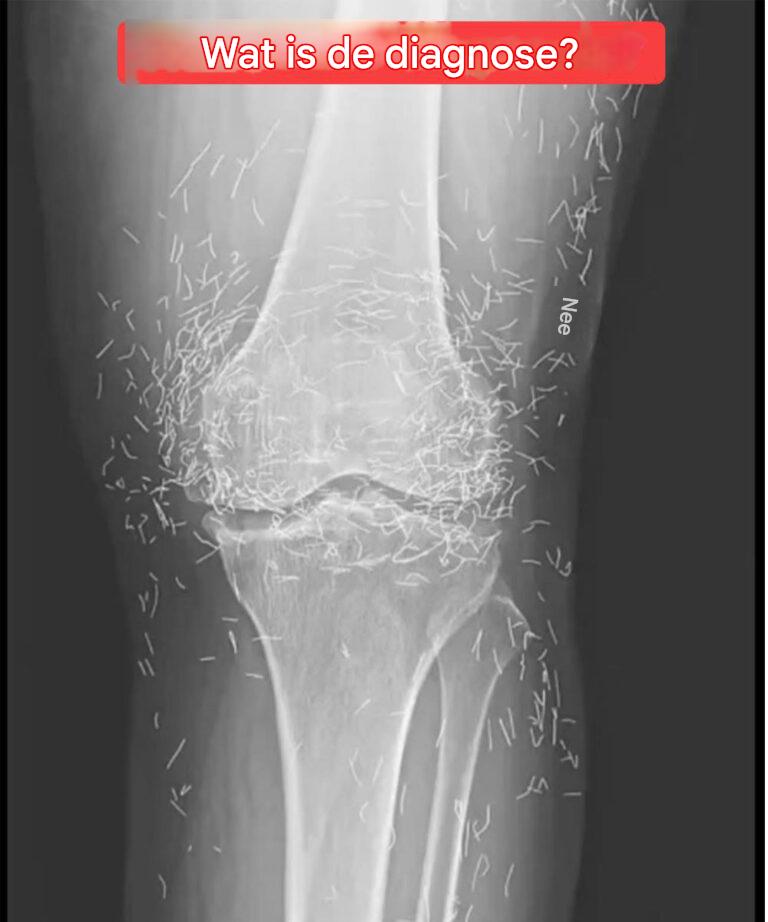

Toen artsen een röntgenfoto bekeken van de knieën van een oude vrouw die last had van ernstige gewrichtspijn, ontdekten ze een goudmijn: honderden kleine gouden acupunctuurnaaldjes waren in haar weefsel achtergebleven.

Toen artsen een röntgenfoto bekeken van de knieën van een oude vrouw die last had van ernstige gewrichtspijn, ontdekten ze een goudmijn: honderden kleine gouden acupunctuurnaaldjes waren in haar weefsel achtergebleven. De 65-jarige vrouw uit Zuid-Korea had eerder de diagnose artrose gekregen, een aandoening waarbij het kraakbeen en de botten in de gewrichten afbreken, wat … Lire plus